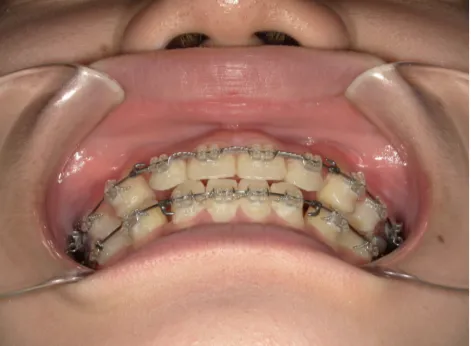

治療後⑩高2:17y7m 抜歯治療終了

口元の治療前後:15y5m→17y7m スッキリしました